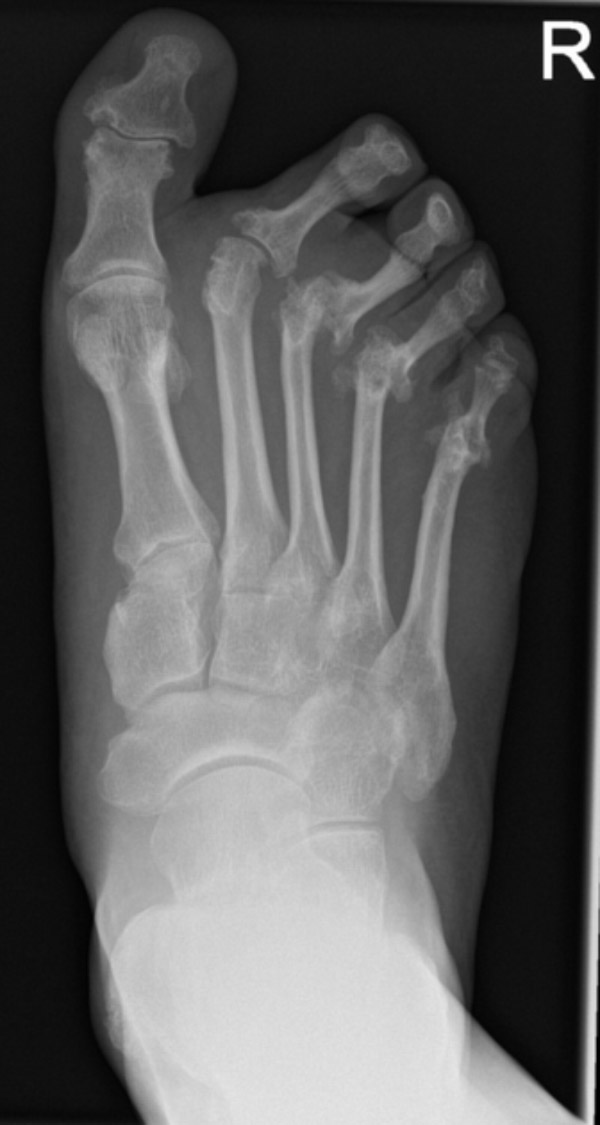

Hình ảnh viêm khớp dạng thấp ở bàn chân và ngón chân cho thấy người bệnh bị chai chân, xuất hiện u ngón chân cái. Các ngón chân trở nên cong, cứng, biến dạng, trở thành ngón chân hình móng vuốt hoặc ngón chân hình búa. Vòm bàn chân có thể bị sụp xuống, khiến bàn chân bẹt, gây đau nhức và khó đi lại (2):

Một số hình ảnh chụp X-quang viêm khớp dạng thấp: